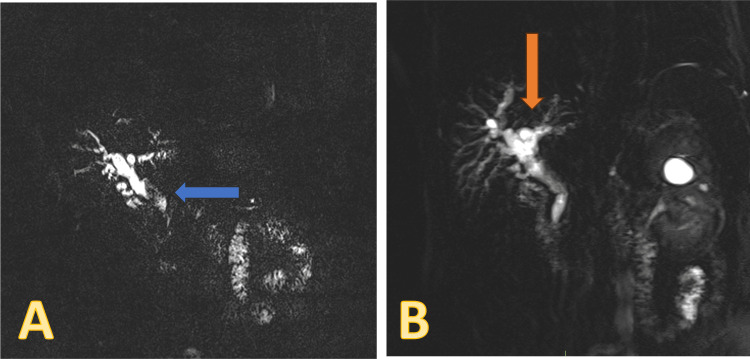

An abdominal CT showed a normal liver with mild intrahepatic biliary duct prominence and evidence of previous cholecystectomy Magnetic resonance cholangiopancreatography (MRCP) showed biliary dilatation disproportionate to post-cholecystectomy status with filling defects within the common bile duct, suggestive of stones (Figure 1).